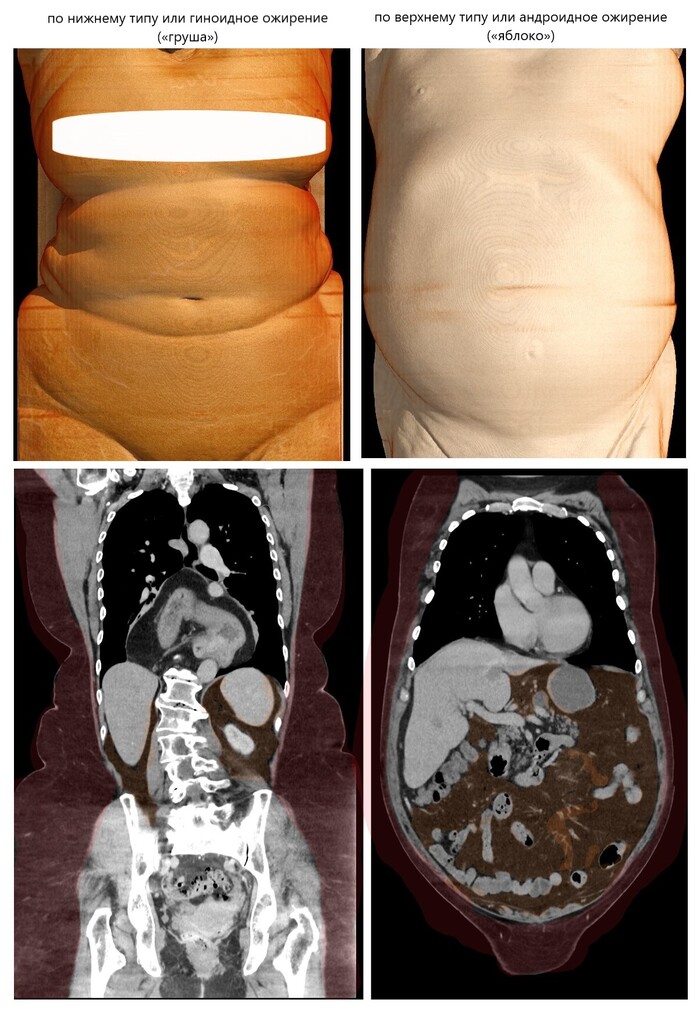

Итак, поступила девочка, 7 лет. После ДТП (переходила дорогу на красный свет, водитель поздно сориентировался и почти на полной разрешённой скорости - 40-50 км/ч - произошёл наезд), обнаружена бригадой скорой без сознания, на месте заинтубирована, в состоянии комы доставлена в больницу. Сердечно-лёгочная реанимация на месте НЕ ПРОВОДИЛАСЬ (остановки сердечной деятельности / дыхания не было).

Сделали компьютерную томографию почти всего тела по протоколу множественной травмы (голова, шея, органы грудной клетки + органы брюшной полости включая позвоночник и таз).